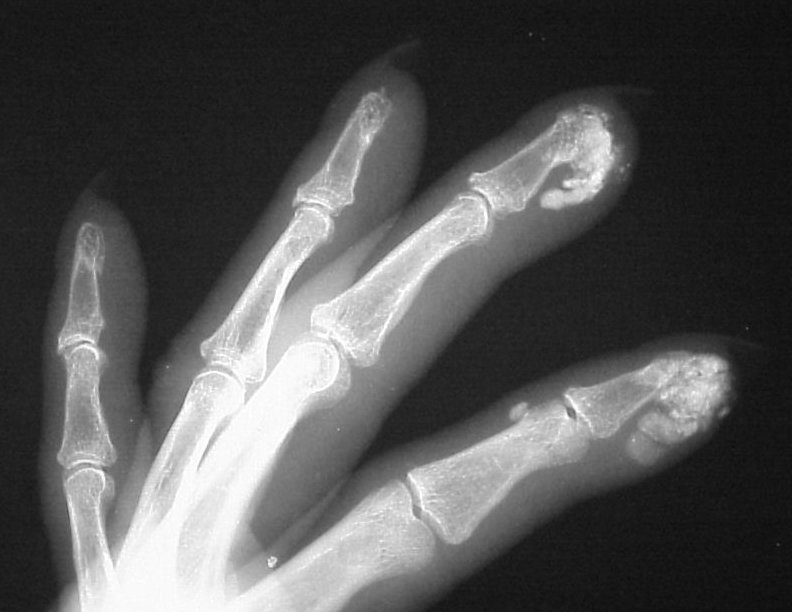

Xrays show extensive soft tissue calcifications of the distal pulp of these fingers.

Soft tissue calcifications are typically diffuse, and can not be simply "shelled out". Thorough excision may lead to extensive skin loss, and partial removal (limited incision and drainage) may be a reasonable compromise approach in selected cases.

Healing ulcerations on the left index and middle fingertips, where calcium deposits have spontaneously drained in the past.